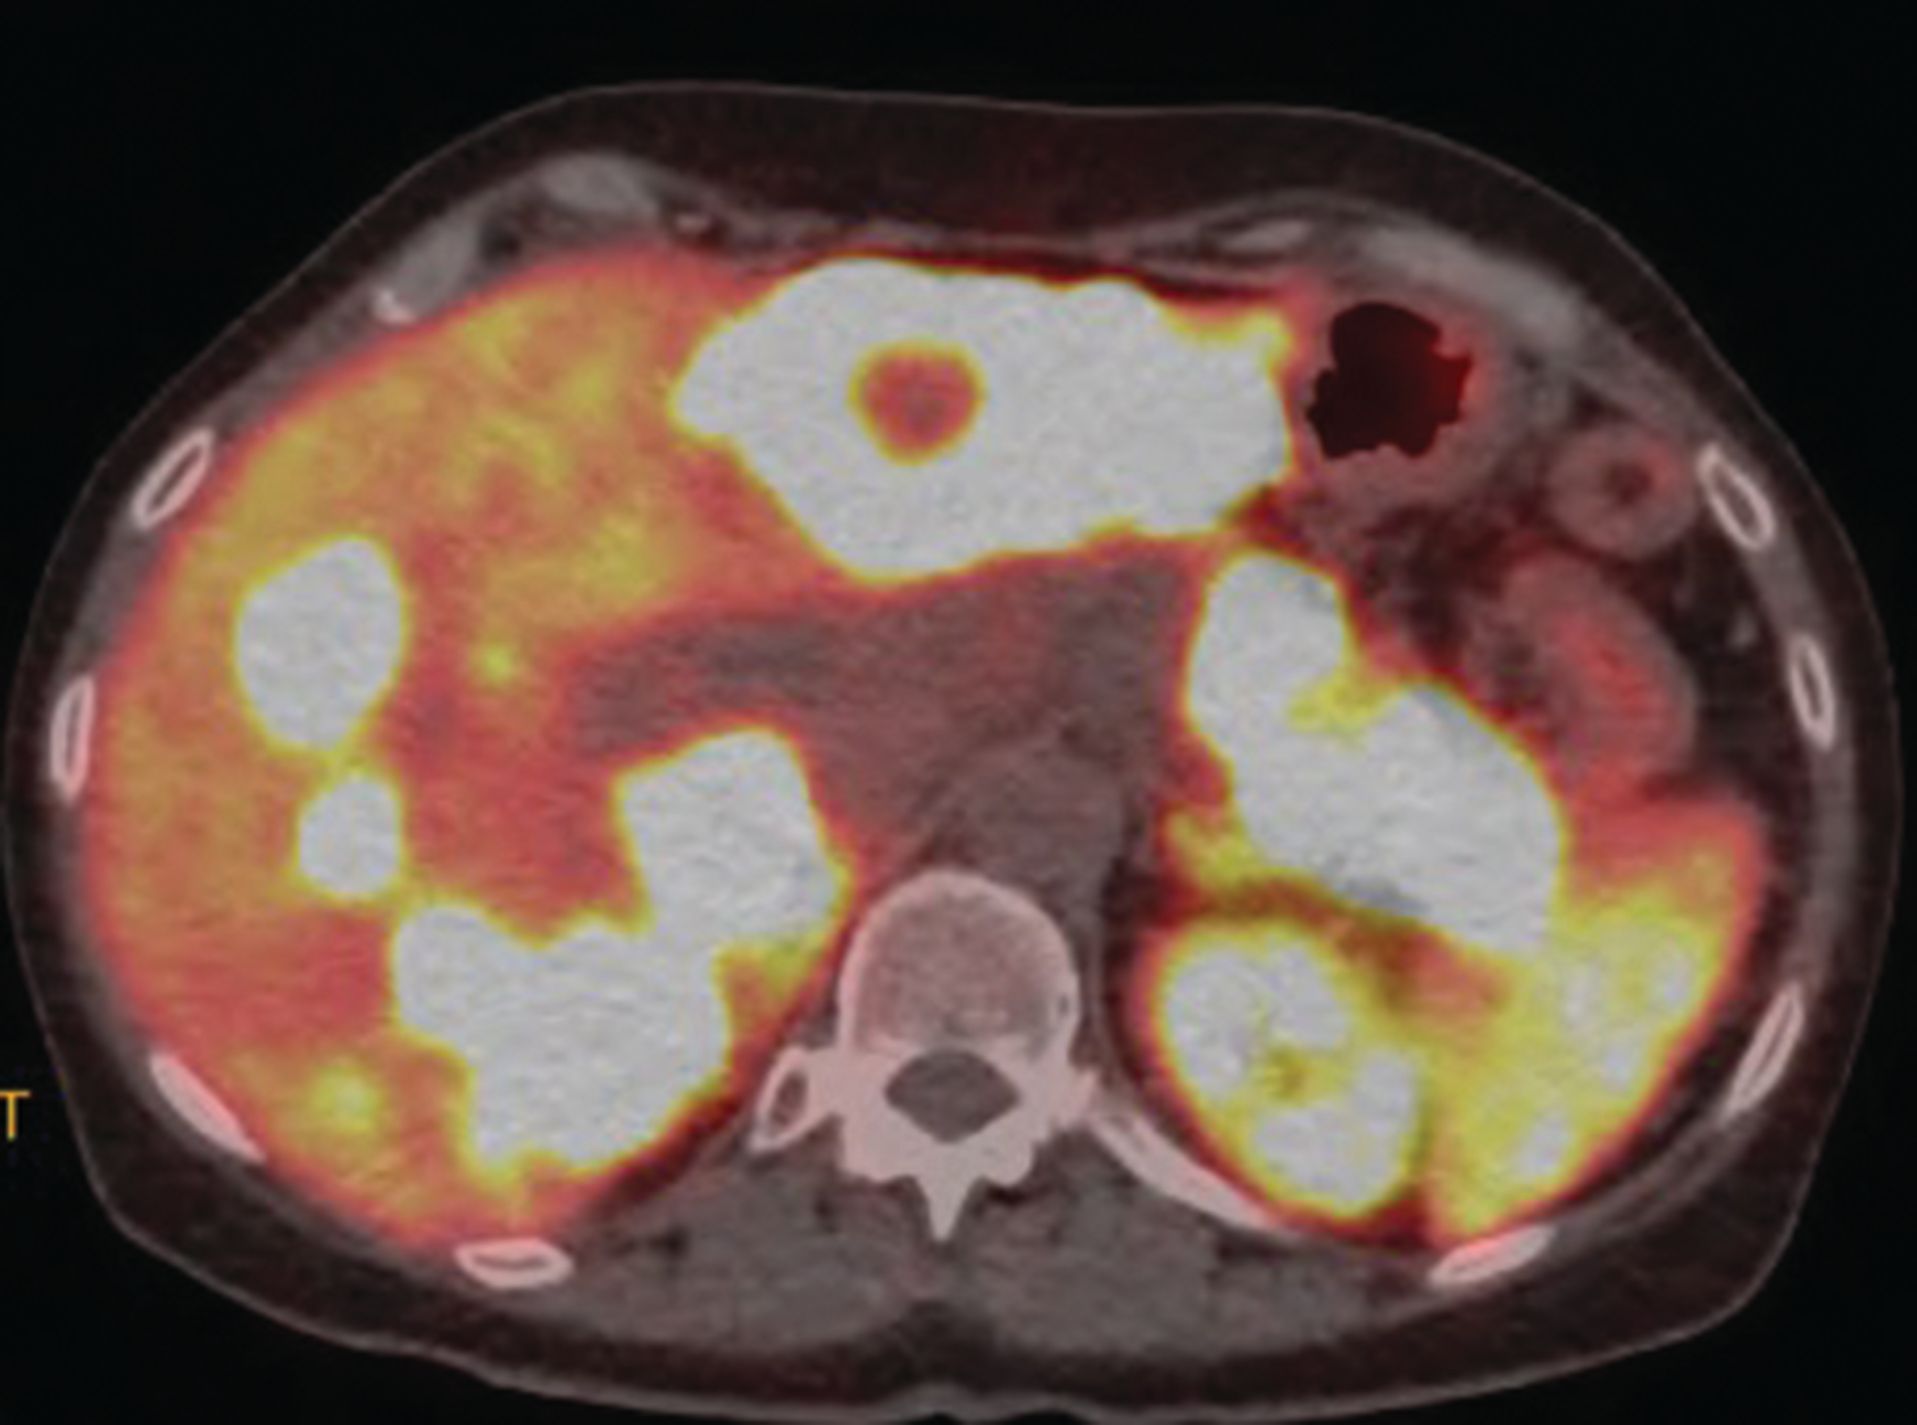

A White woman aged 62 years noted poor appetite, occasional nausea, vomiting, indigestion, and a 30-pound weight loss starting 6 months prior to her diagnosis. Initial evaluation, including upper and lower endoscopies, revealed Barretts esophagus with no dysplasia, a cecal polyp, and negative celiac disease markers. Treatment with proton pump inhibitors did not help her symptoms. As time passed, she noted occasional epigastric and right upper quadrant abdominal pain. Further evaluation with ultrasound and a CT scan of the abdomen revealed a large necrotic mass in the pancreatic body/tail extending to the splenic hilum with invasion into the spleen, as well as multiple enhancing lesions throughout the liver(Figure 1A). A CT-guided biopsy of a liver lesion revealed a metastatic, well-differentiated, high-grade (grade 3) NET with rosette formation, high mitotic rate (more than 20 per high power field), and a Ki-67 index of 30% (Figure 2 A,B). Further work-up with 68gallium 68-dotatate PET-CT confirmed a large pancreatic body/tail PET avid mass with direct extension involving the splenic hilum and multiple hepatic metastases. (Figure 1B). Ultrasound of the thyroid and parathyroid glands andMRI of the brain was negative. Serum gastrin, glucagon, and vasoactive intestinal peptide levels were normal. She had no fasting or nocturnal hypoglycemia. Serum chromogranin A level was elevated at 754 ng/mL (normal 0-103). A genetic consultation and work-up by our certified genetic counselor did not reveal any familial neuroendocrine syndrome.

Figure 1B. Large pancreatic body/tail PET avid mass with direct extension into splenic hilum. Multiple PET avid hepatic metastases.